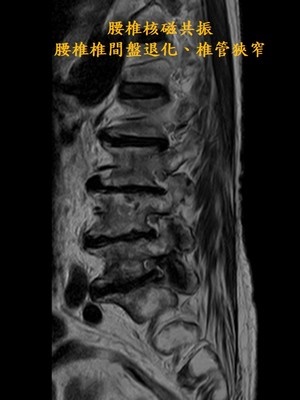

一旁陪伴的兒子林先生表示,其實母親三年前因腰椎椎管狹窄壓迫到神經導致她腰痛難受,母親痛到吃不下,走不了,坐著痛、站著也痛,不僅吃止痛藥沒有用,嚴重時只能躺在床上至少有二十二小時,還瘦了七公斤,看過多位醫師都說只能透過開刀來改善,但母親不想手術,因為擔心開刀的手術風險以及可能復發等後遺症,為了母親的生活品質,他尋覓合適的治療方式,還好當時透過網路找到有做疼痛介入性治療的王柏凱主任,就帶著母親來求醫。

王柏凱主任說,當時詹女士的第五腰椎跟薦椎間中間的椎間盤嚴重退化,因神經孔過小壓迫到神經,導致左邊的坐骨神經痛,當時做了硬脊膜外注射、增生療法等治療,疼痛明顯改善,但是效果只能維持約三個月;詹女士因為有膝蓋的骨內注射療法大大改善疼痛的經驗,與病人討論後,在今年七月的腰椎治療,也加入了骨內注射治療,如今詹女士已五個月沒感受到腰痛了。